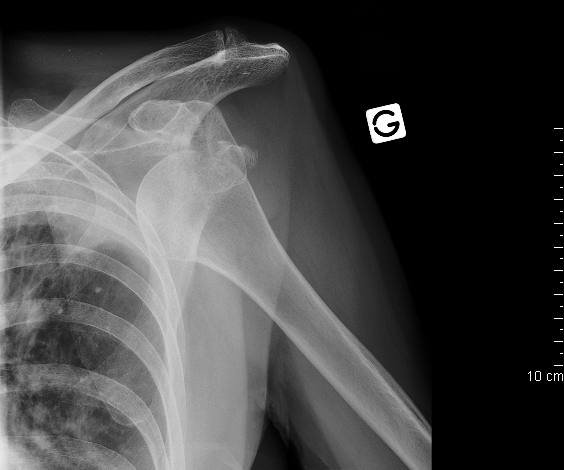

operative therapie arthroskopie schulterarthroskopie gelenkzentrum mittelbaden